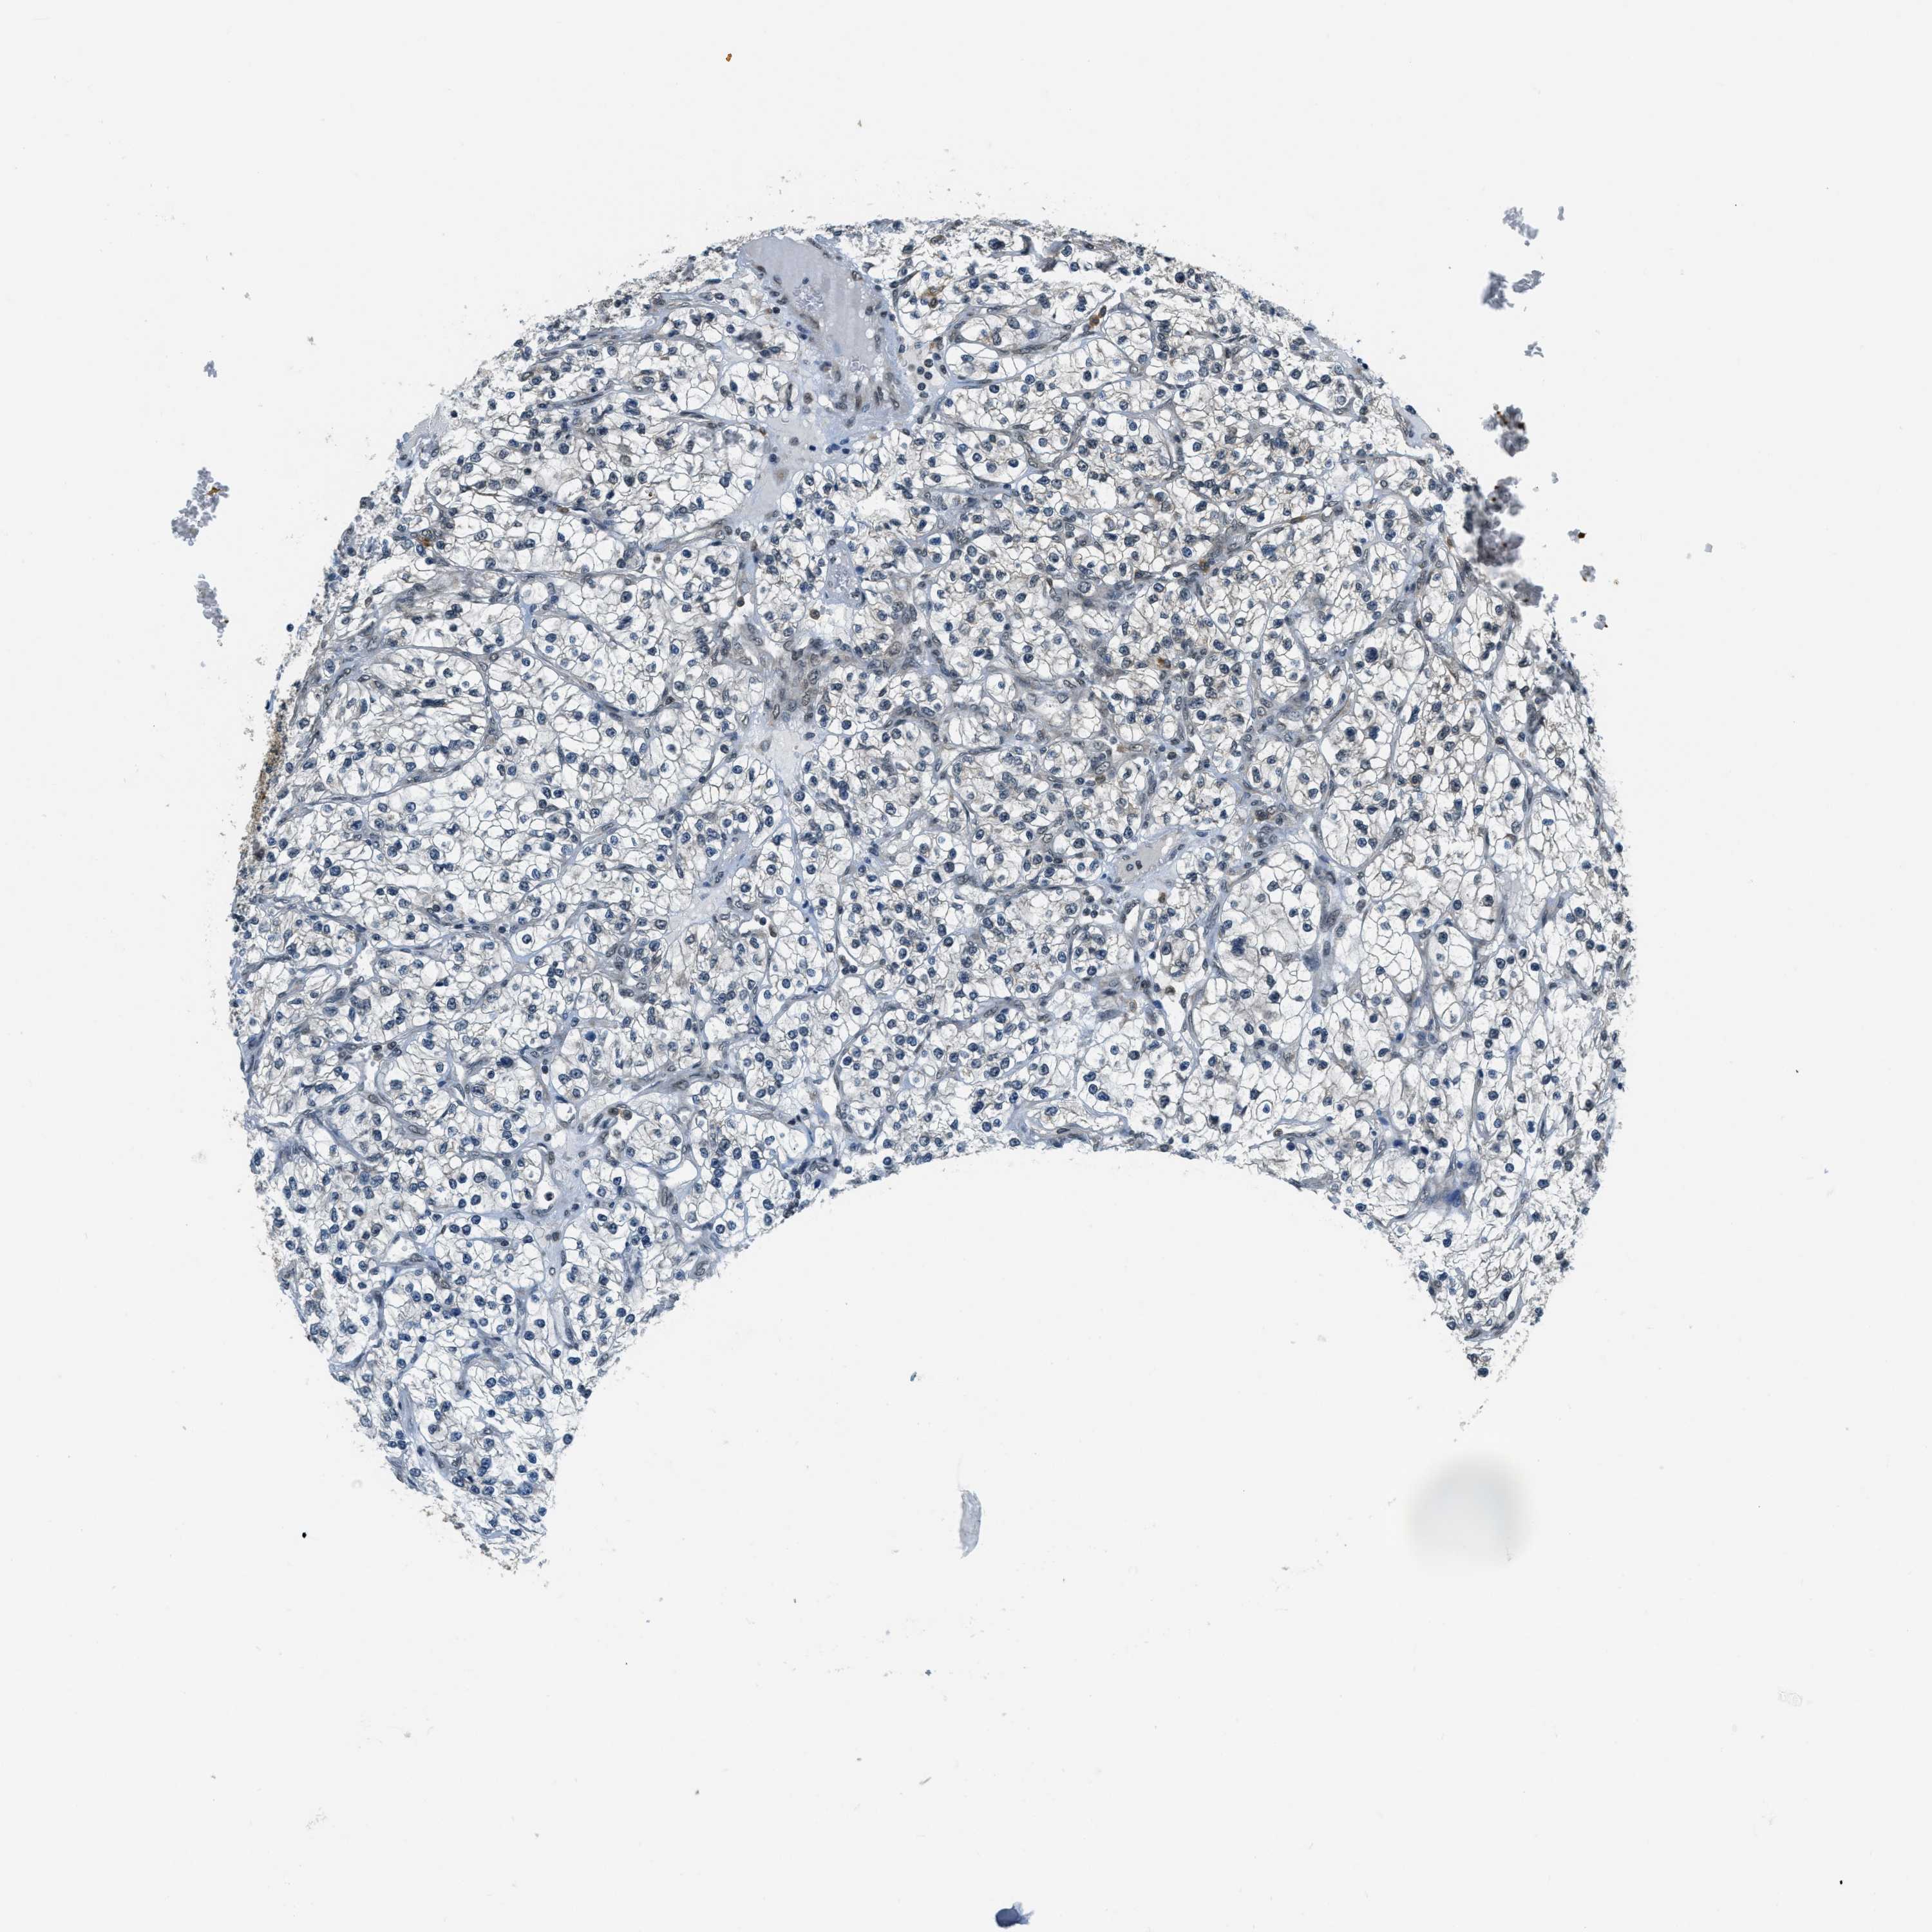

KIDNEY RENAL CLEAR CELL CARCINOMA (VALIDATION) - Interactive survival scatter ploti

The Survival Scatter plot shows the clinical status (i.e. dead or alive) for all individuals in the patient cohort, based on the same data that underlies the corresponding Kaplan-Meier plots. Patients that are alive at last time for follow-up are shown in blue and patients who have died during the study are shown in red.

The x-axis shows the expression levels (FPKM) of the investigated gene in the tumor tissue at the time of diagnosis. The y-axis shows the follow-up time after diagnosis (years). Both axes are complimented with kernel density curves demonstrating the data density over the axes. The top density plot shows the expression levels (FPKM) distribution among dead (red) and alive patients (blue). The right density plot shows the data density of the survived years of dead patients with high and low expression levels respectively, stratified using the cutoff indicated by the vertical dashed line through the Survival Scatter plot. This cutoff is automatically defined based on the FPKM cutoff that minimizes the p-score. The cutoff can be changed by dragging the vertical line or by entering a cutoff value in the square labeled "Current cut-off".

Under the Survival Scatter plot the p-score landscape (black curve; left axis) is shown together with dead median separation (red curve; right axis). Dead median separation is the difference in median mRNA expression between patients who have died with high and low expression, respectively. It is calculated as follows: median FPKM expression of dead patients with high expression - median FPKM expression of dead patients with low expression. This is intended to aid the user in visually exploring custom cutoffs and the associated p-scores and dead median separation.

Individual patient data is displayed and can be filtered by clicking on one or more of the category buttons on the top of the page. Categories describing expression level and patient information include: high, low, alive, dead, female, male and tumor stages. The scale of the x-axis can be toggled between linear and log-scale by clicking on the "x log" button. Mouse-over function shows TCGA ID, patient information and mRNA expression (FPKM) for each patient.

& Survival analysisi

Kaplan-Meier plots summarize results from analysis of correlation between mRNA expression level and patient survival. Patients were divided based on level of expression into one of the two groups "low" (under cut off) or "high" (over cut off). X-axis shows time for survival (years) and y-axis shows the probability of survival, where 1.0 corresponds to 100 percent.

RAB11FIP1 is not prognostic in Kidney Renal Clear Cell Carcinoma (validation)

Best expression cut offi

Based on the FPKM value of each gene, patients were classified into two groups and association between prognosis (survival) and gene expression (FPKM) was examined. The best expression cut-off refers the FPKM value that yields maximal difference with regard to survival between the two groups at the lowest log-rank P-value. Best expression cut-off was selected based on survival analysis .

When clicking on this number, the vertical dashed line indicating cut-off, the interactive survival plot, and the Kaplan-Meier curve will be adjusted to show results based on the best expression cut-off.

: 16.44

P scorei

Log-rank P value for Kaplan-Meier plot showing results from analysis of correlation between mRNA expression level and patient survival.

N/A

TCGA RNA samplesi

RNA-seq data is reported as average FPKM (number Fragments Per Kilobase of exon per Million reads), generated by the The Cancer Genome Atlas (TCGA) .

Normal distribution across the dataset is visualized with box plots, shown as median and 25th and 75th percentiles. Points are displayed as outliers if they are above or below 1.5 times the interquartile range. FPKM values of the individual samples are presented next to the box plot.

Average pTPM 18.3

Number of samples 100